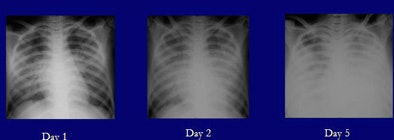

The investigators studied 98 x-rays of the 14 patients, all of whom were under age 35 and had been admitted to Ho Chi Minh City Hospital in Vietnam. The victims included three children 12 years of age or younger. One of those children survived, she said, but nine of the patients died.

"Characteristically," Qureshi said, "the patients who died came in very sicker, got even sicker and died -- within nine days." The survivors, however, who were hospitalized for as long as 42 days, developed other complications -- pleural effusions and cavitations or areas of deep-seated infections, she said.

| The H5N1 avian flu virus is endemic in the poultry stocks of nine Southeast Asian countries. Chest x-rays of patients infected with the virus may demonstrate focal consolidation, reticulonodular shadowing, pleural effusion and/or thickening, pneumothorax, lobar collapse, and lymphadenopathy. The appearance and pathological progression of disease on chest x-rays differed between patients who succumbed to avian flu (above) and those who survived infection (below), primarily in terms of continued progression among nonsurvivors, and in the total number of involved segments. Evidence of consolidation in four or more lung segments was significantly associated with mortality. Survivors and nonsurvivors alike were all treated with broad-spectrum antibiotics and the antiviral drug Tamilflu (Roche, Basel, Switzerland). All images courtesy of Dr. Nagmi Qureshi. |